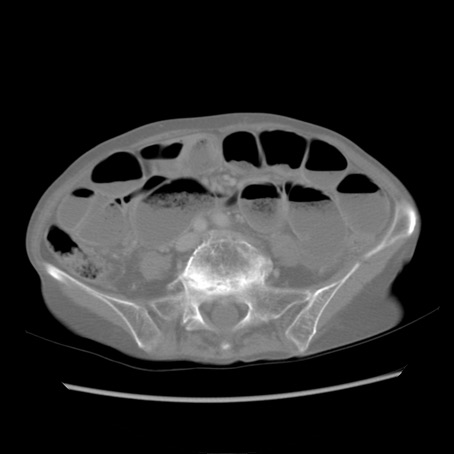

症例25(横断像)

【症例】80歳代女性

【主訴】胸のつかえ感

【現病歴】約9時間前に食後から胸のつかえた感じあり、嘔吐あり、来院。

【既往歴】胃癌(全摘)、胆摘、虫垂炎

【身体所見】心窩部に圧痛あり、反跳痛なし。

【データ】WBC 5700、CRP 0.05